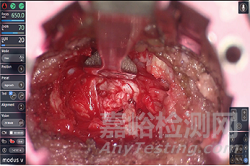

Modus X該平臺(tái)可使用熒光引導(dǎo)手術(shù)能夠?qū)崟r(shí)改善腫瘤組織分化。通過新鏡片進(jìn)行手術(shù),具有4K 3D光學(xué)、27倍放大、自動(dòng)圖像聚焦、語音引導(dǎo)等功能。

Modus X除4K 3D光學(xué)、放大27倍外還具有650mm工作距離,并在98%的手術(shù)沒有背部和頸部疼痛,具有適宜人體使用的設(shè)計(jì)。此外, 與顯微鏡檢查相比,頸部屈曲拉傷所花費(fèi)的時(shí)間減少了24%。

應(yīng)用先進(jìn)的4K 3D光學(xué)和熒光可視化技術(shù),對(duì)此便可實(shí)時(shí)改善組織分化。

Modus X改進(jìn)了光學(xué)系統(tǒng),并為狹窄通道入路設(shè)計(jì)了機(jī)器人定位,除提高了切除范圍,還減少了主動(dòng)回縮。